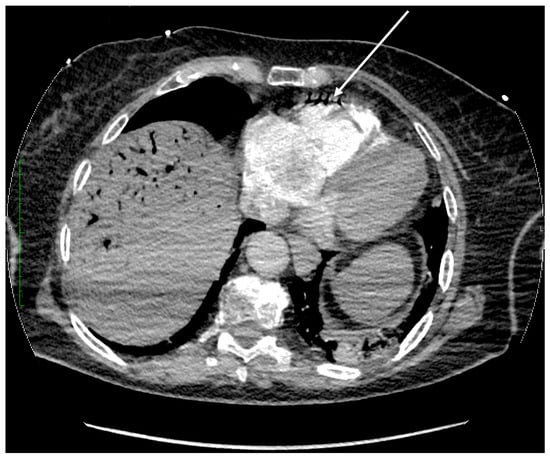

Figure 4. Axial plane of the chest CT angiography scan after intravenous contrast administration (soft tissue window). Massive aerobilia is observed within the biliary tree. Air is also present in the right ventricle (arrow).

The most common mechanism of air embolism involves gas bubbles entering the inferior vena cava and then the right heart cavities. The use of highly blood-soluble carbon dioxide aims to reduce the risk of this complication. When there is a massive accumulation of gas bubbles in the cavities of the right heart and pulmonary artery system, the course of the embolism is often detrimental. By performing a CT angiography of the thorax shortly after the SCA, we were able to capture CO2 gas in the right ventricle, as seen in Figure 4.